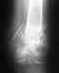

По снимкам - несостоятельный остеосинтез. Нижний отломок большеберцовой кости стержень не удерживает, тем более и винтов в нем нет. Есть неустраненное значительное смещение. Возможно, стержень уже сломан (есть его деформация).

Остеосинтез надо переделать, стержень взять потолще и ввести поглубже, устранив попутно все смещения, и запереть в нижнем отломке 3 винтами. Кальций Д3 не нужен, мумие вообще нонсенс (XXI век на дворе!).